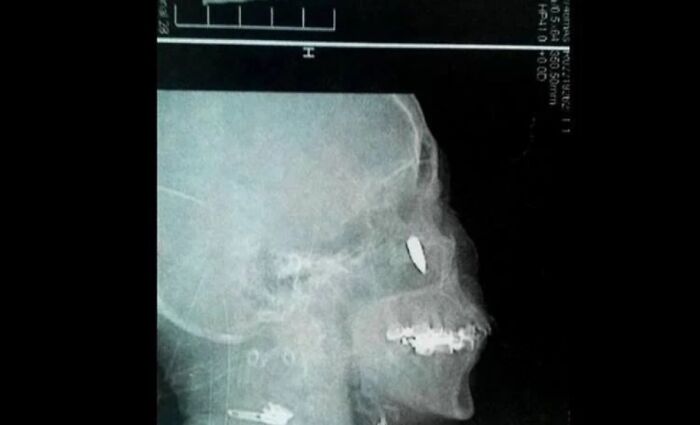

#64

A Chinese woman with chronic rhinitis was suffering from headaches and breathing issues. An exploratory x-ray revealed a bullet lodged in her head by her nostril. She then remembered back 48 years ago to when she was 14, and walking along a path. The woman felt a stinging pain in her temple and started to bleed. She thought she’d been hit by a pebble; so her family cleaned her up and threw a bandage on it. Apparently she was shot.